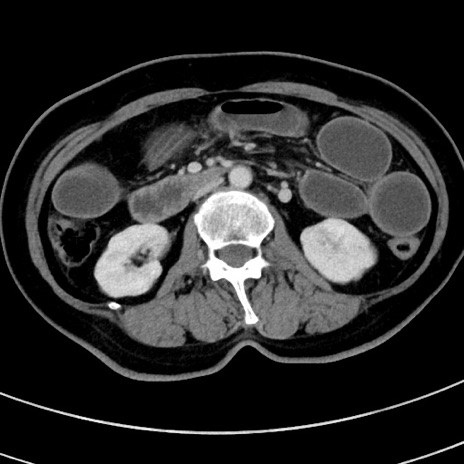

冠状断像

【症例】 60歳代女性

【主訴】むかつき、みぞおちの痛み

【現病歴】3日前よりむかつきがあり、食事がとれない。

【既往歴】糖尿病

【身体所見】発熱なし、心窩部圧痛軽度あるも、腹膜刺激症状なし。

【データ】WBC 7400、CRP 1.92